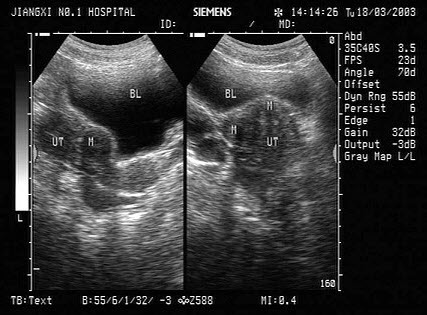

35、单项选择题 患者王某,干下型室间隔缺损,左向右分流,用超声检测,要了解其峰值跨隔压差,应检测什么参数()

女性,43岁,因月经量多,经期时间长,月经周期短就诊。体检:子宫体积大,表面不平整。结合超声图像,最可能的诊断为()

A.子宫内膜癌

B.宫颈癌

C.多发性子宫肌瘤

D.葡萄胎

E.子宫腺肌瘤